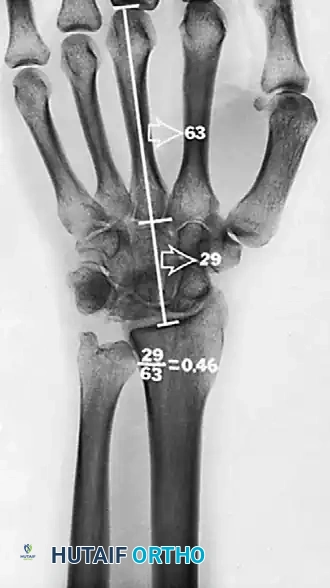

Hultén described a biomechanical condition known as the "ulna-minus variant" (negative ulnar variance). He found that in 78% of patients with Kienböck disease, the ulna was shorter than the radius at their distal articulation, compared to only 23% in normal wrists. Negative ulnar variance increases the shear and compressive forces transmitted directly from the radius to the lunate, accelerating fragmentation.

A common fracture pattern is the anterior pole type, which isolates the anterior pole from the remaining bone. The compressive force exerted by the capitate distracts the fracture, diminishing the likelihood of healing. As the dorsal portion of the lunate collapses, the anterior pole may be extruded volarly. Furthermore, the ratio of carpal height to the length of the third metacarpal is reduced (normal is 0.54 ± 0.03), indicating overall carpal collapse.